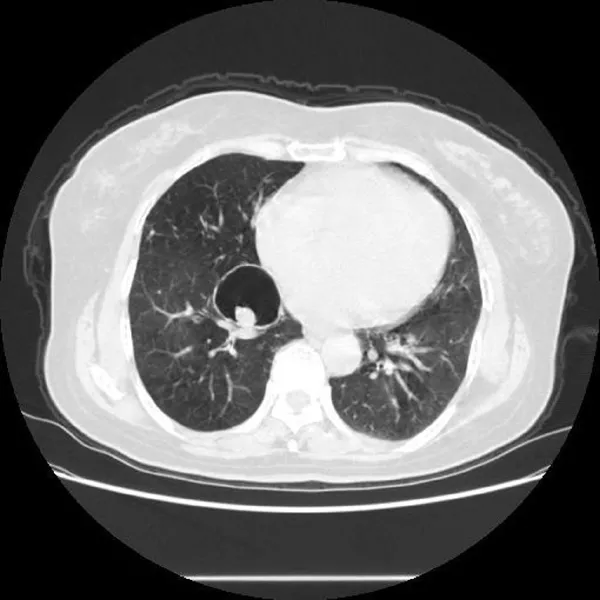

邵女士,36岁,是一位上海市的居民。她在经历了连续两周的咳嗽、咽部干痒以及黄痰后,前往医院进行了检查,最终被诊断为社区获得性肺炎(非重症)及咽炎。经过医生的综合治疗与药物使用,邵女士的症状得到明显缓解。接下来,我们一起看看这些药物是如何帮助她战胜疾病的。